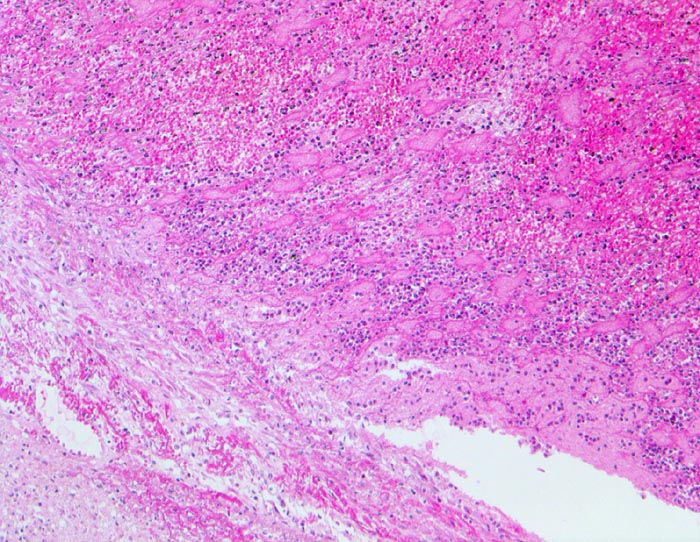

Papillarmuskel und Vorderwand zeigen territoriale Koagulationsnekrosen, welche vom Rand her von neutrophilen Granulozyten infiltriert werden (blauer Saum).

Ein Teil der neutrophilen Granulozyten ist bereits zerfallen (Kerntrümmer)

Das nekrotische Myokard ist erkennbar an seiner dunkleren Färbung (Hypereosinophilie) und einer Abblassung oder dem Verschwinden der Zellkerne.

Herzmuskelzellen mit Kontraktionsbandnekrosen vor allem in den Randbereichen des Infarktareals.